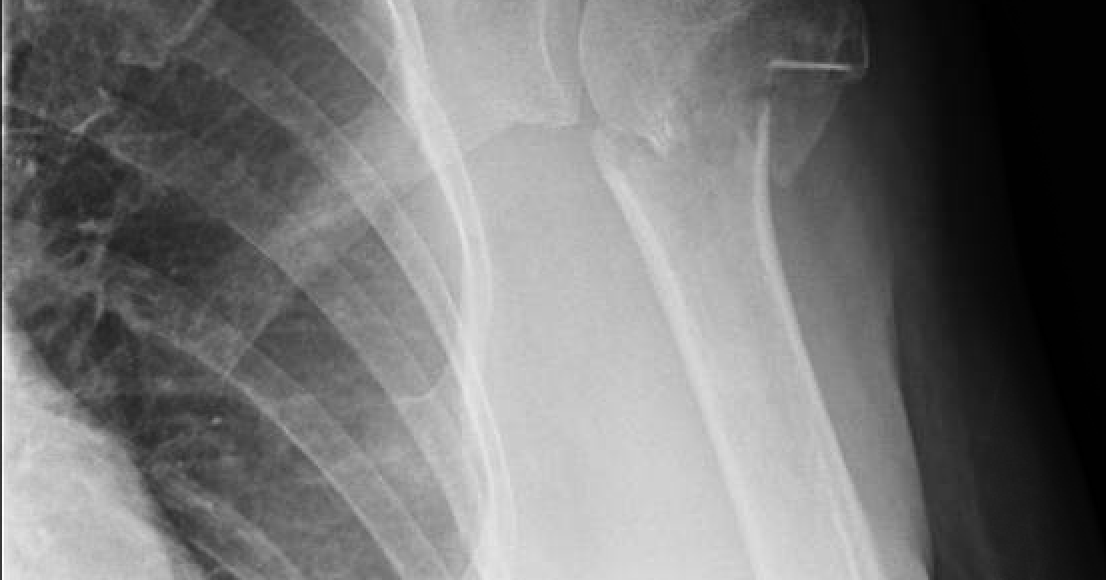

rradiographshowsaproximalhumerusfracture Shoulder & Elbow Collar And Cuff Fracture  Most clavicle fractures occur when a fall onto the shoulder or an outstretched arm puts enough pressure on the bone that it snaps or breaks. This this is usually worn.  rhcg fracture management guidance.  most fractures involve a short period of immobilisation, usually wearing a collar and cuff for comfort. Rhc fracture clinic pathway & how to arrange. Collar And Cuff Fracture.